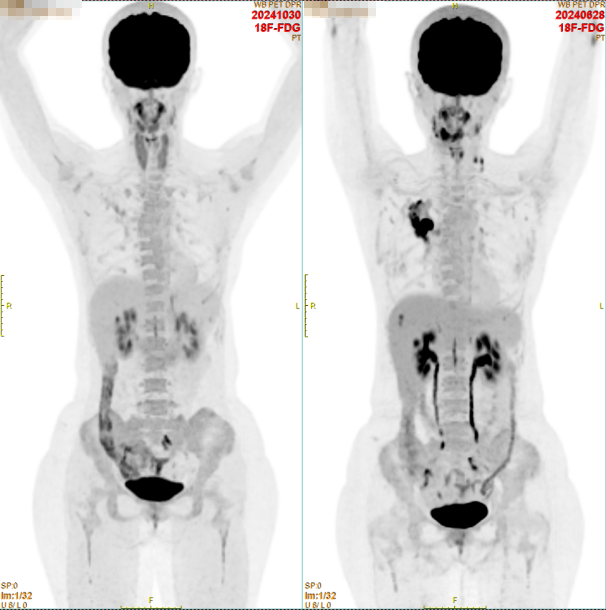

4个疗程后复查全身PET/CT,结果提示:

①原右上肺癌灶,体积较前缩小,代谢较前明显降低。

②原右肺门及左侧锁骨上高代谢淋巴结现代谢降至本底水平。

③原肝S8高代谢结节,现未见显示。